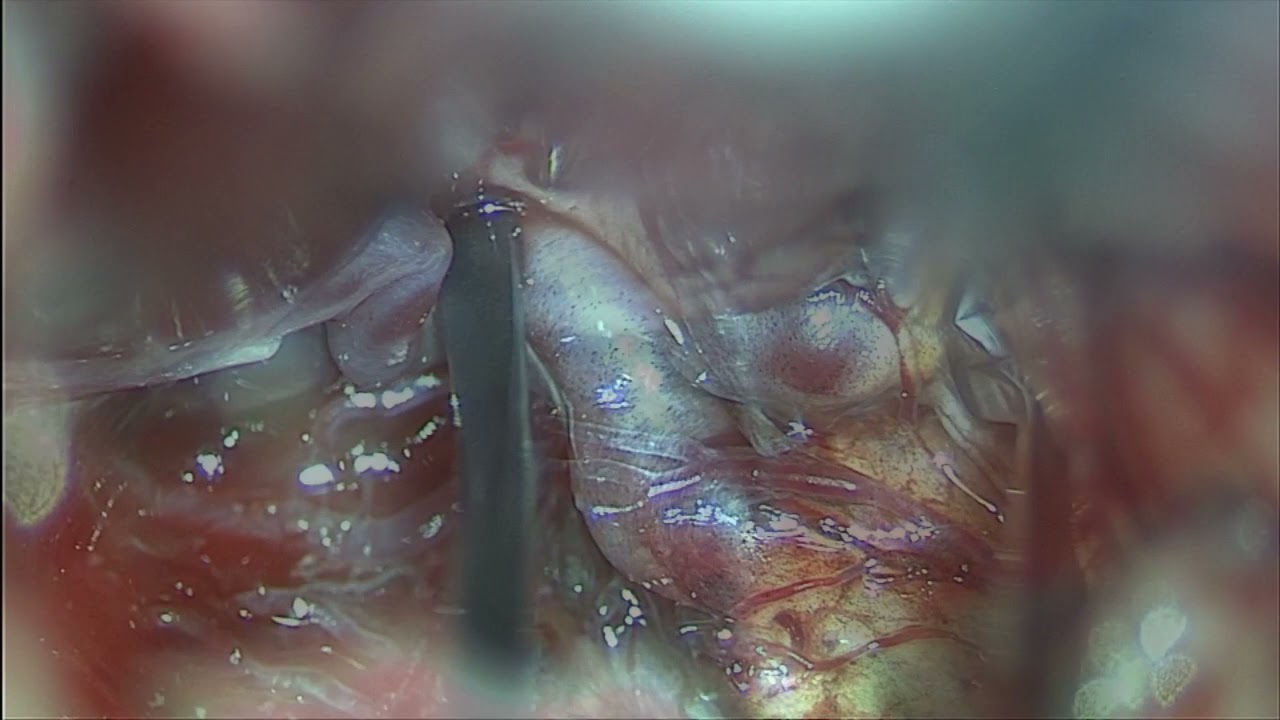

STA-PCA bypass and proximal occlusion for giant basilar top aneurysm plus multiple aneurysms